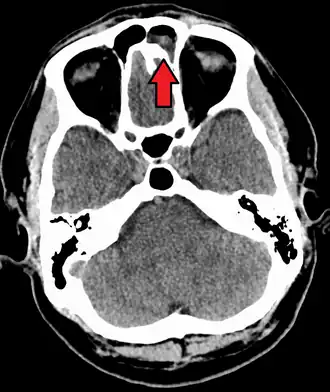

Intracranial complications

The proximity of the sinuses to the brain makes brain infections one of the most dangerous complications of acute bacterial sinusitis, especially when the frontal and sphenoid sinuses are involved. These infections can result from invasion of anaerobic bacteria through the bones or blood vessels. Abscesses, meningitis, and other life-threatening conditions may occur. In rare cases, mild personality changes, headache, altered consciousness, visual problems, seizures, coma, and even death may occur.[33]

Maxillary sinusitis caused by a dental infection associated with periorbital cellulitis -